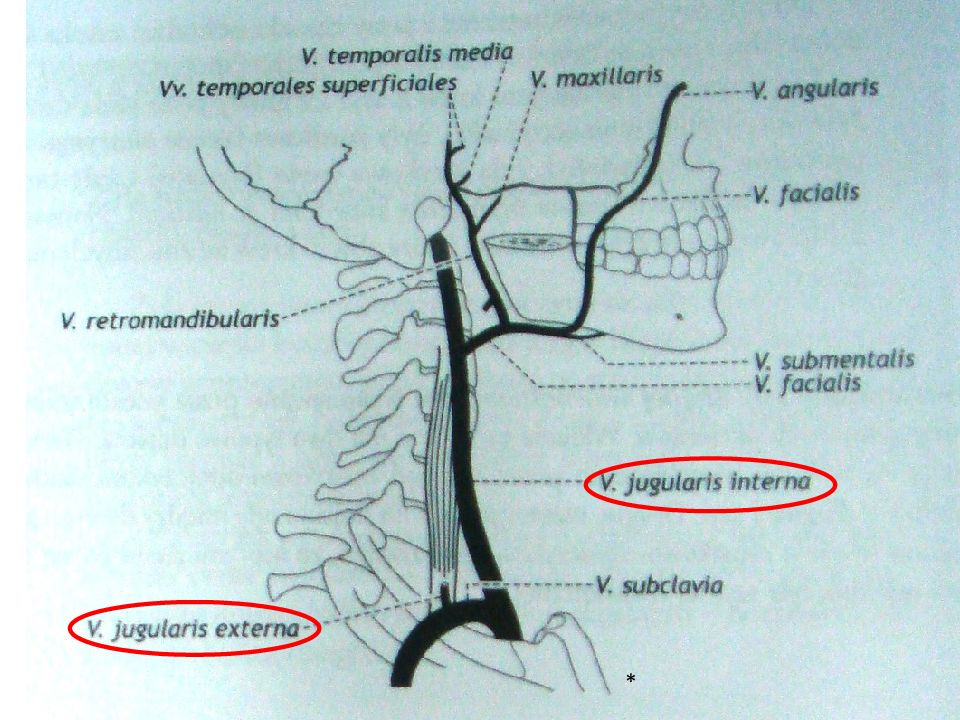

Анатомия внутренней яремной вены: КТ изображения